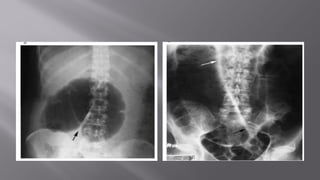

 Jejunum shows concertina effect due to valvulae conniventes

(Herring bone pattern)—by the valves of Kerckring.

 Ileum is smooth and characterless (by Wangensteen).

 Large bowel shows haustration.

 Distended caecum is shown as round gas shadow in the right

iliac fossa. Dilated caecum signifies large bowel obstruction.